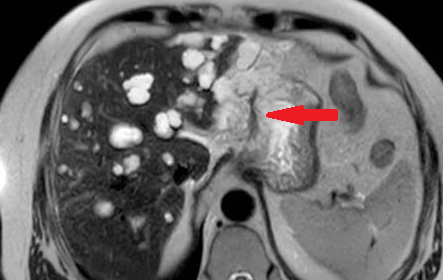

Polycystic liver disease. Red arrow. Infected hepatic cyst (Courtesy Dr. V. Penopoulos)